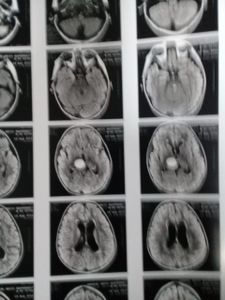

Sou pedro, pai do príncipe gabriel que foi Diagnosticado com glioblastoma astrocitoma LLA (câncer no cérebro) sou pai solteiro a mãe do Gabriel faleceu em 2021 e agora estou sozinho cuidado dele, estou com muitos gastos tenho aluguel para pagar tenho que compra medicamentos e comidas para casa no momento estou desempregado e meu filho precisa de cuidados, minha situação não está fácil, peço ajuda de todos nesse momento, quem puder ajudar com qualque centavos ficarei muito grato, PRECISO DE AJUDA PARA MEU FILHO !!! quem puder ajudar com alimentos ou roupas tambem preciso, vou deixar meus dados para quem puder ajudar ...